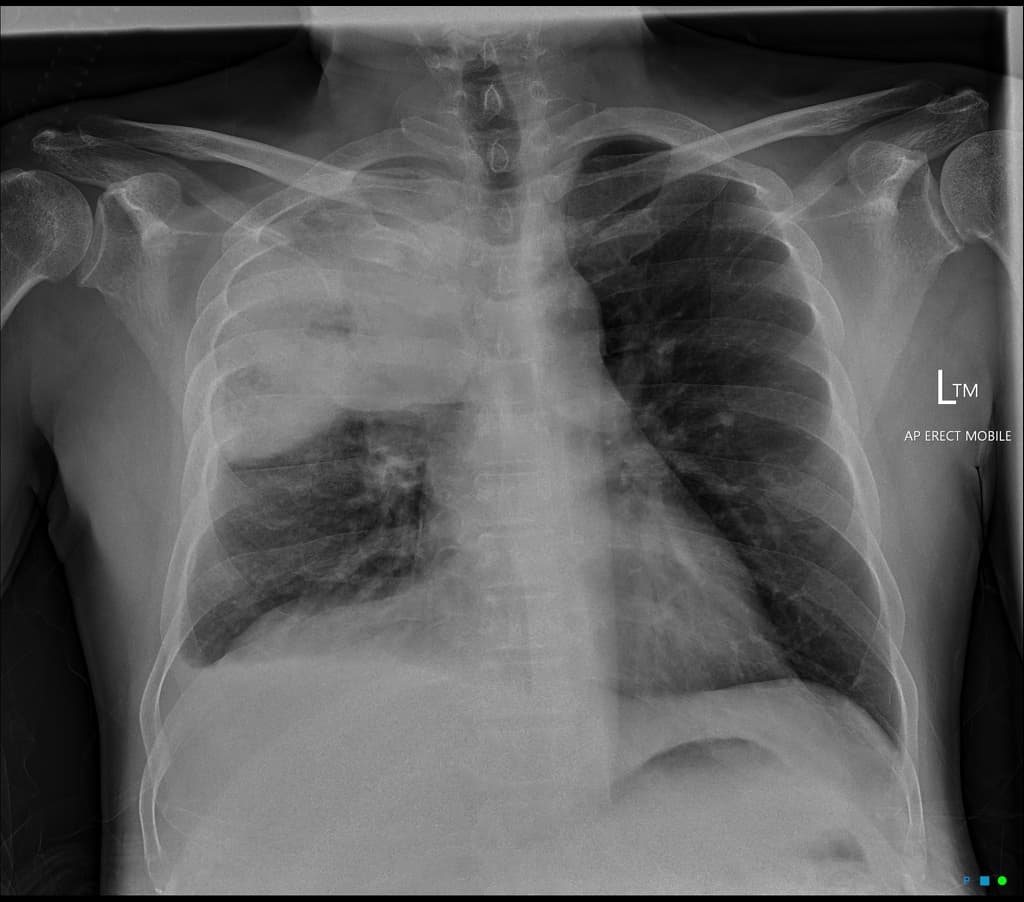

- Có các vùng mờ đậm không đồng đều dạng khoảng khí (patchy airspace opacities) và dày lên kẽ (interstitial thickening) lan tỏa ở cả hai phổi.

- Không thấy tràn dịch màng phổi (pleural effusion) hay hạch trung thất (lymphadenopathy).

- Tim không giãn, các cấu trúc trung thất ở vị trí bình thường.

- Xương lồng ngực không thấy tổn thương tiêu xương hay gãy.

Viêm phổi nguyên phát dạng không điển hình (Primary atypical pneumonia)

- "Chụp hình thường thấy các mờ kẽ và mờ khoảng khí dạng không đều, song song ở cả hai phổi, dù triệu chứng nặng nhưng dấu hiệu thực thể có thể nhẹ."